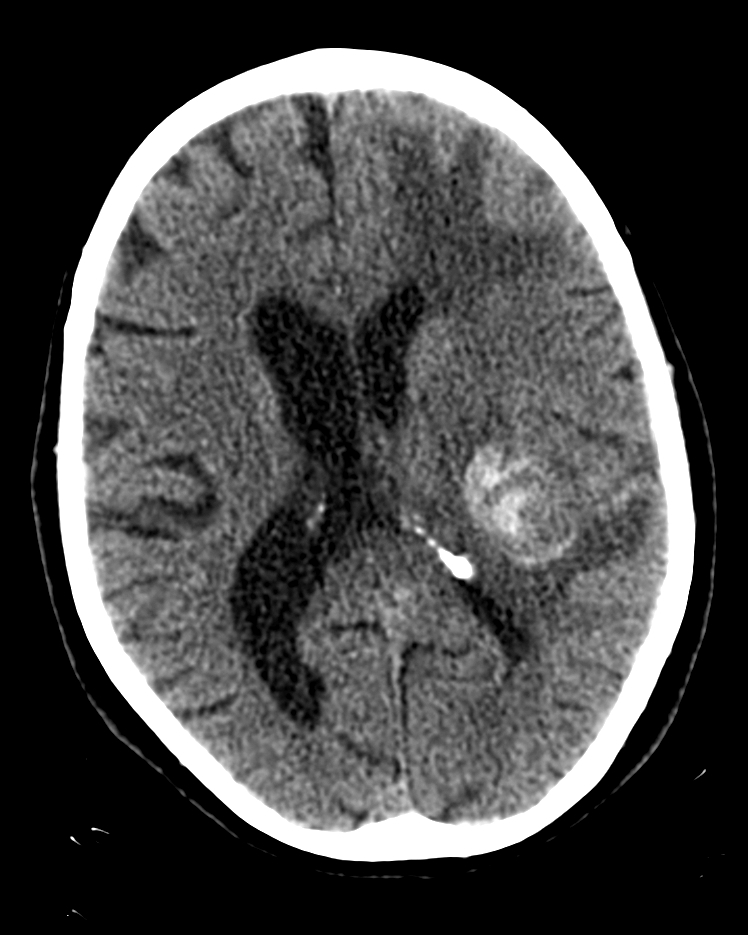

Cerebral metastasis: lung cancer | Image | Radiopaedia.org

El Blog de Isa y Juan: Metástasis cerebral de melanoma maligno